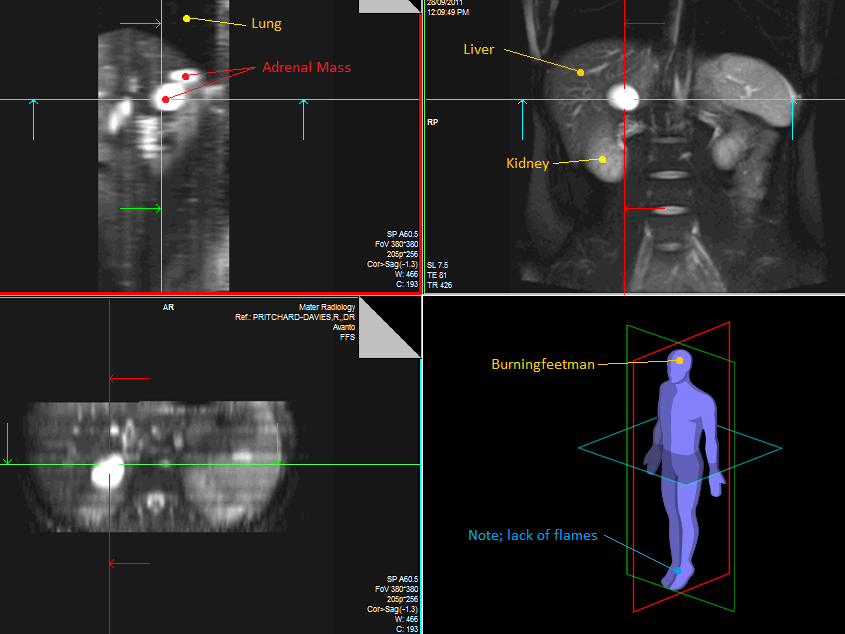

Right Adrenal Mass

I was diagnosed with a right adrenal mass in late 2011, after experiencing many misc symptoms for about a decade. After many blood tests were taken, only one came back positive, for the hormone estradiol, which is relatively toxic at heightened levels, especially in men. Surgery is tomorrow for the tumours removal.